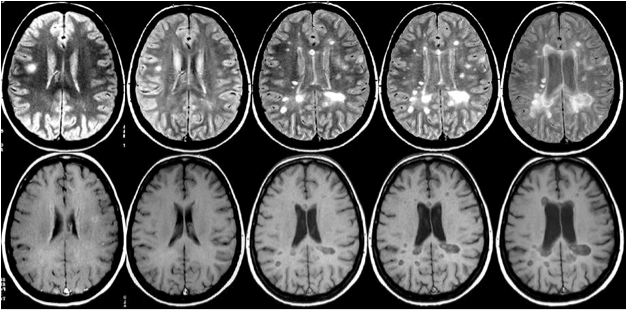

Diffusion And Magnetization Transfer Imaging Detects Spinal ...

Diffusion and magnetization transfer imaging detects spinal cord lesions in amyotrophic lateral sclerosis P-F. Pradat1, J. Cohen-Adad2,3, Magnetization transfer ratio and myelin in postmortem multiple sclerosis brain. Ann Neurol, 2004. 56(3): p. 407-15. ... Read Content